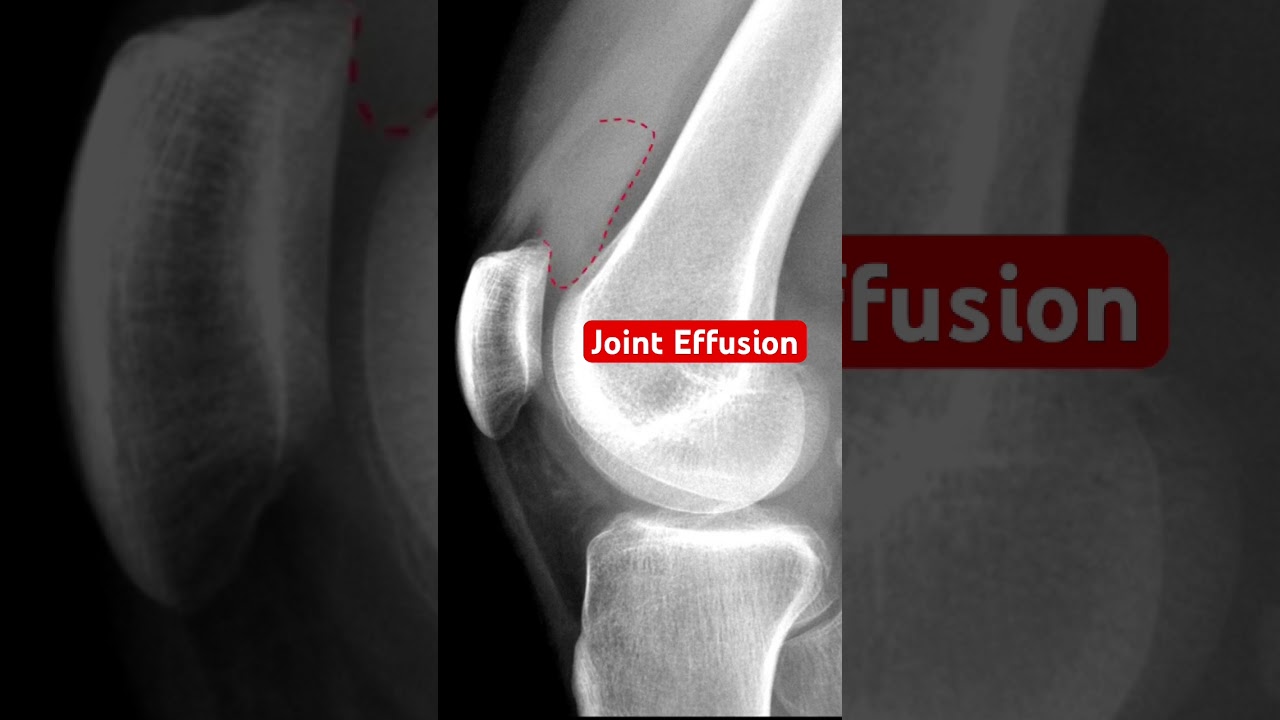

Joint Effusion Treatment Find out what joint effusion is and how it affects your joints, with insights on symptoms, diagnosis, and treatment for effective relief. Joint effusion is where the fluids in the tissues around your joint increase causing your knee, shoulder, ankle or other joint swells up. treatments help heal the swelling by addressing the cause.

Joint Effusion Treatment Knee Effusion Synovitis Volume Measurement In this article i answer some of the questions you may have about joint effusion, and i will rely on my knowledge as a radiographer and on scientific medical studies. Joint effusion is the abnormal collection of fluid within a joint capsule, often caused by injury, arthritis, infection, or systemic conditions. learn how to identify, diagnose, and treat this condition, and when to seek urgent care. Define joint effusion (swollen joint) and explore the medical strategies needed to address the root cause and find lasting relief. The combination of intra articular corticosteroids, appropriate oral medications, and physical therapy provides the most comprehensive approach to managing joint effusion and improving patient outcomes.